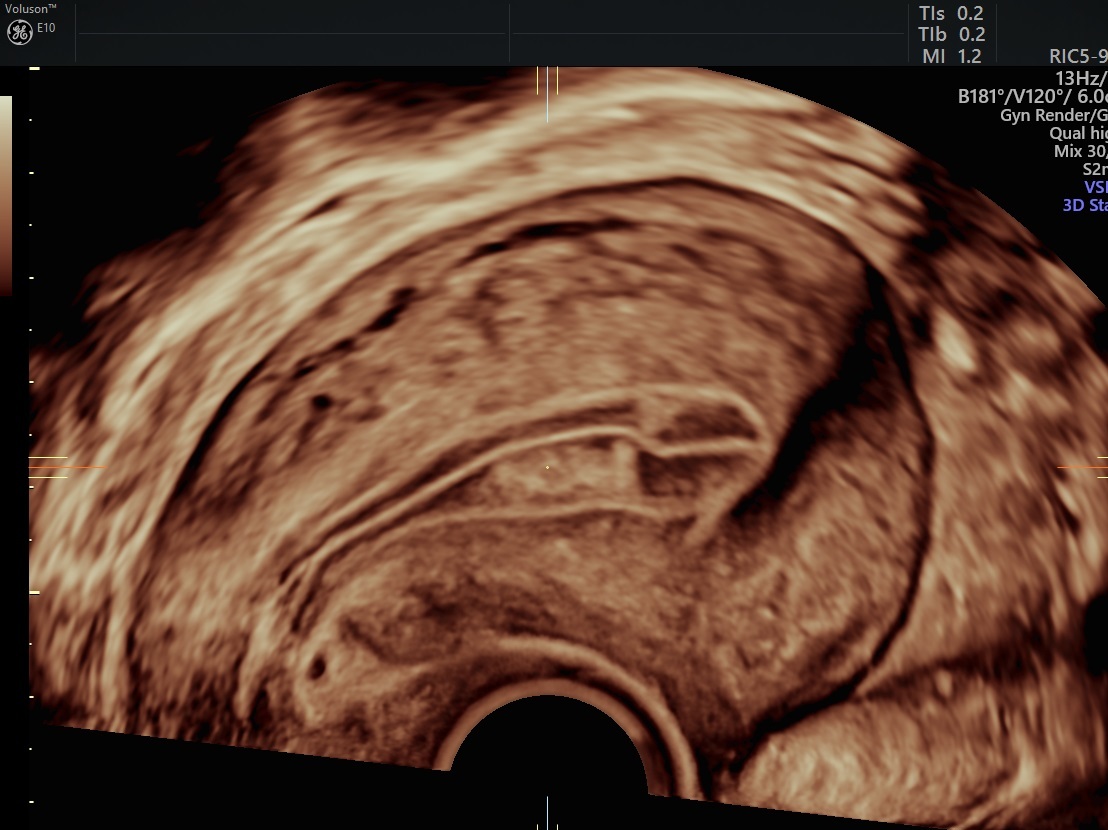

From www.volusonclub.net

Postmenopausal Bleeding Treatment The Power of Ultrasound Empowered Postmenopausal Bleeding Uterine Fibroids    while it’s extremely rare, fibroids can sometimes form in people who are postmenopausal but it’s currently unclear why this occurs. Provide general advice on sources of information and support, such. However, a person should seek medical advice if they have bothersome.  there can be several causes of postmenopausal bleeding. The most common causes are: Treatment may not be. Postmenopausal Bleeding Uterine Fibroids.